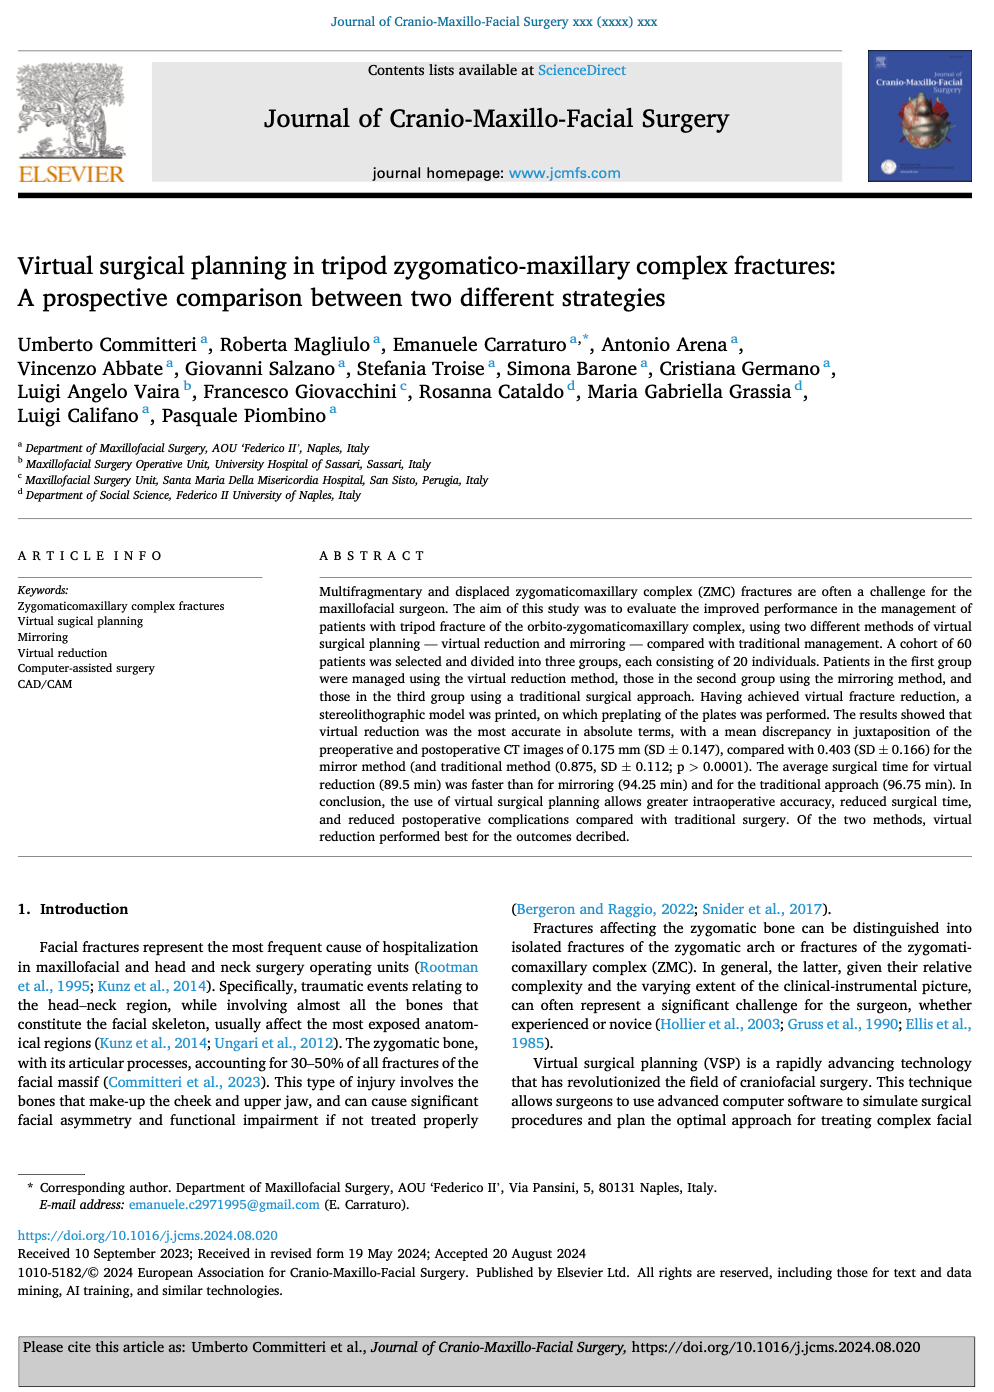

L’articolo pubblicato di recente

Virtual surgical planning in tripod zygomatico-maxillary complex fractures: A prospective comparison between two different strategies

The use of virtual surgical planning allows greater intraoperative accuracy, reduced surgical time, and reduced postoperative complications compared with traditional surgery. Of the two methods, virtual reduction performed best for the outcomes decribed